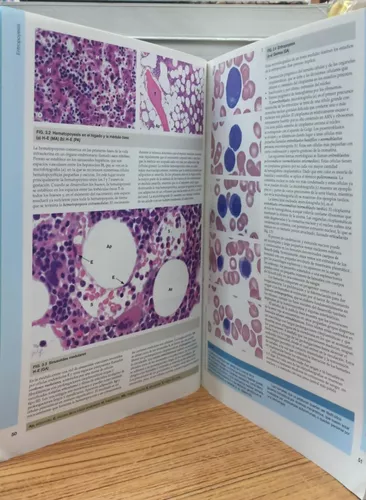

Estos libros suelen ofrecer una gran cantidad de ilustraciones y microfotografías que facilitan la visualización de las estructuras microscópicas, ayudando a los estudiantes a comprender mejor conceptos abstractos. Además, ofrecen explicaciones claras y concisas, lo que facilita el proceso de aprendizaje y ayuda a retener la información.

- Este libro es ampliamente utilizado en programas de histología y es conocido por su enfoque claro y su abundancia de imágenes y diagramas. Ofrece una comprensión sólida de los conceptos histológicos y la correlación con la anatomía funcional.

- Este libro se centra en la relación entre la estructura y la función de los tejidos y órganos. Ofrece una excelente combinación de texto explicativo y atlas en color para ayudarte a comprender la histología en contexto.

- Un libro ampliamente utilizado y respetado que presenta la histología de una manera clara y accesible. Incluye imágenes y diagramas detallados que facilitan la comprensión de los tejidos y sus funciones.

- Un libro que se enfoca en la presentación visual de la histología con imágenes a todo color y diagramas claros. Es especialmente útil para aquellos que aprenden mejor a través de material visual.